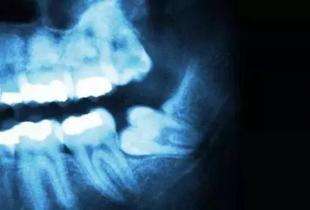

随着人类不断进化,人体颌骨的逐渐变小,当轮到最后一颗牙要萌出时,颌骨所留下的空位已不多了,很难让它正常萌出,这就造成了“阻生牙”。在颌骨内由于位置不当,不能萌出到正常咬合位置,被称为阻生牙或阻生齿。最常见的阻生牙是下颌第三磨牙,其次是上颌第三磨牙和上颌尖牙。据统计,成人中阻生牙的发生率为20%。这种阻生牙和覆盖在它上面的牙龈之间,很容易藏污纳垢,孳生细菌,引起口臭、龋坏,当身体抵抗力下降时,常常会发生炎症。